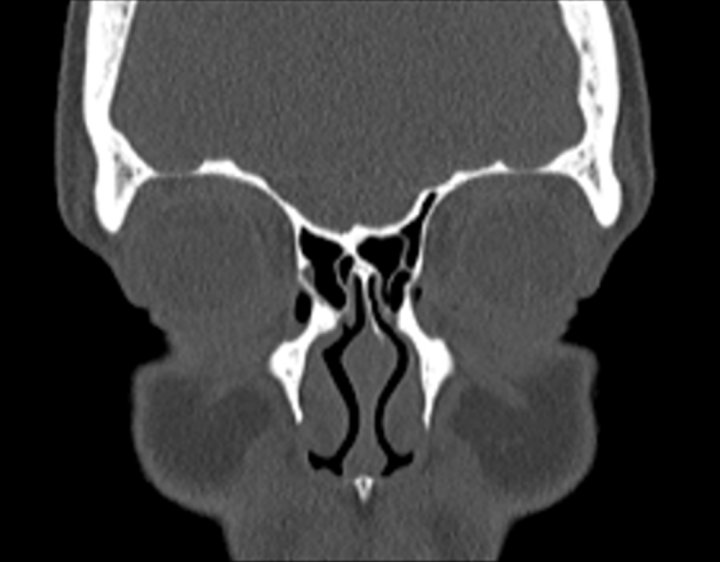

Click any image for labels.